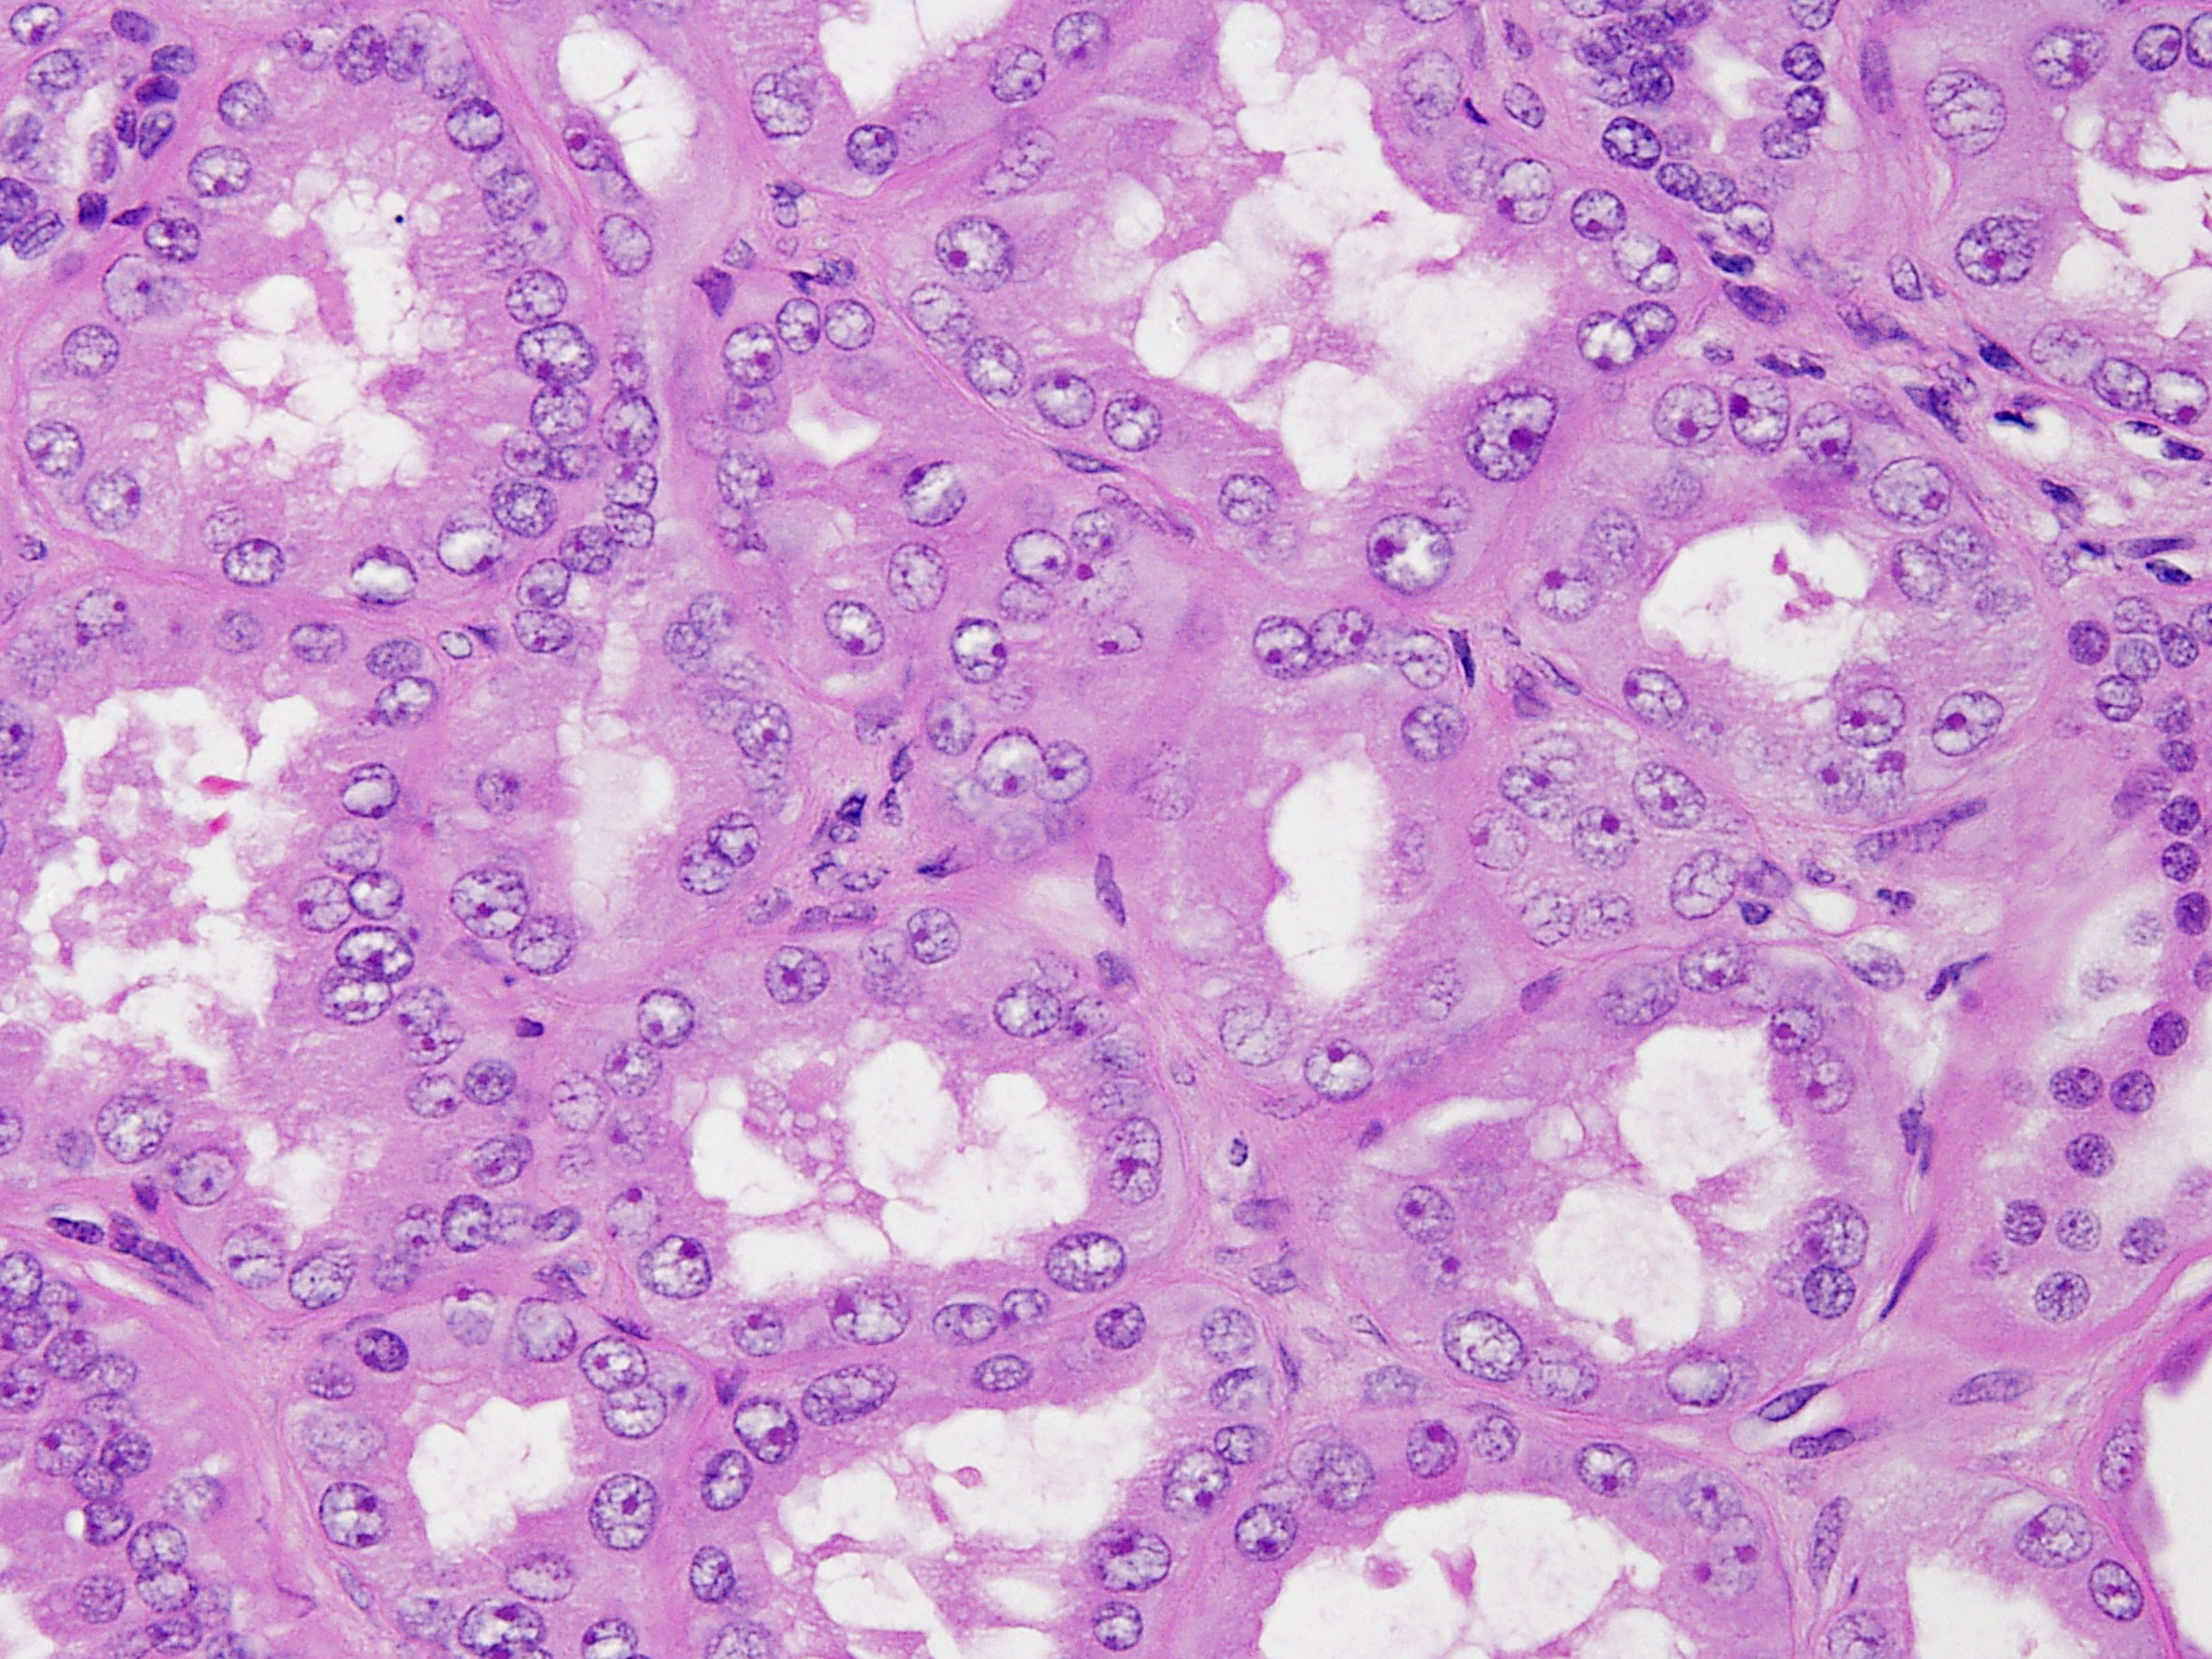

Consensus grade: Tubulocystic RCC

| Pathologist 10 | Hereditary leiomyomatosis and RCC-associated RCC | Not typical |

I would support my diagnosis by FH gene analysis...it could also be high grade tubulocystic RCC |

but need to rule out HLRCC |

tubulocystic vs HLRCC |

Tubulocystic renal cell carcinoma